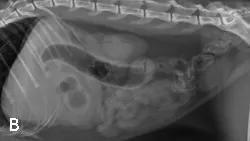

A) Right radiograph, B) Left radiograph, and C) Ventrodorsal radiograph

Abdominal radiography: Left/right lateral and VD views.

Radiographic Findings: The stomach (St) and duodenum (D) are severely distended with fluid and gas, suggesting intestinal obstruction or possibly pancreatitis with secondary ileus.

There is a 1.5-cm rounded opaque structure (arrows) in the caudal abdomen, to the left of the descending colon on the VD view. It is partially obscured by feces in the colon (C) on the left lateral view. The remaining organs and serosal detail appear normal.

Comments: We often perform left and right lateral radiographic views of the abdomen in cases of suspected GI foreign bodies and obstructions since the fluid and gas disperse into different portions of the GI tract. For example, any gas in the stomach rises to the pylorus (P) in left lateral recumbency and may outline a foreign body anchored to this region; this is particularly useful in suspected linear foreign bodies, which typically anchor to the tongue or pylorus and subsequently plicate varying degrees of small intestine.